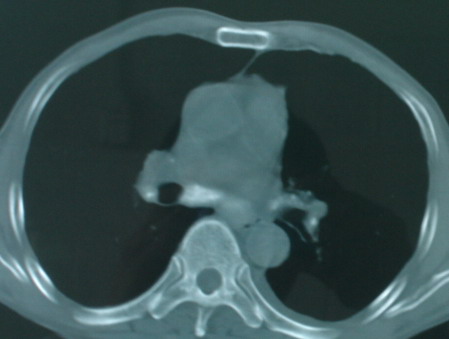

以下是引用医影拾贝在2008-6-3 18:48:00的发言:[br]双上肺弥漫性小结节影,纵隔窗内钙化淋巴结影,考虑血播性tb可能性较大,不除外肺ca可能

以下是引用卜一在2008-6-3 19:33:00的发言:[br]双肺结节,以双上肺分布为多,期间搀杂片状致密影及索条致密影。考虑:继发性肺结核伴血型播散可能性大。不除外肺泡ca的可能!另:椎体退变!

以下是引用panyishengct在2008-6-3 21:09:00的发言:[br]双上肺弥漫性小结节影,纵隔窗内钙化淋巴结影,考虑矽肺或/和tb可能性较大,不除外肺ca可能。腰椎考虑退变。 [br][br]